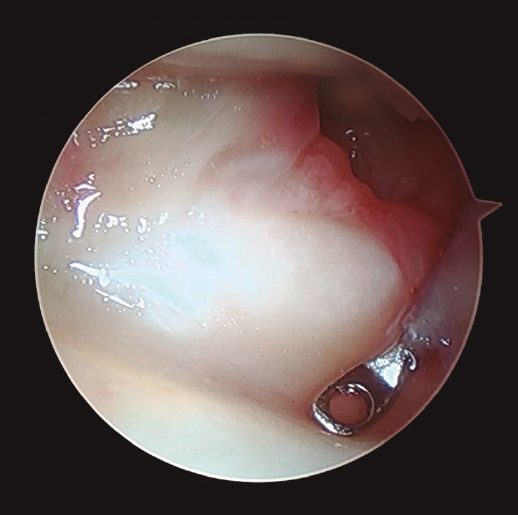

Figura 4. Desde el portal de visión radiocarpiano 3-4 se explora con el instrumental en el portal 6R el complejo del fibrocartílago triangular, observando pérdida de tensión del mismo.

- La pérdida de tensión del CFCT (signo del “trampolín”) con posibilidad de introducir el instrumental artroscópico por debajo del mismo (prueba del “gancho”)(26,27)(Figura 4). De acuerdo con la clasificación de Palmer(24), estas lesiones se trataron de la siguiente manera: tanto las lesiones de tipo IA como ID se trataron mediante un desbridamiento simple con sinoviotomo de 2,5 mm(26,27,28). En el caso de las lesiones de tipo IB y siempre que se observó una prueba del “gancho” positiva, se realizó una reinserción mediante sutura a cápsula articular o un reanclaje a fóvea, según correspondiese en cada caso(26,27,28).